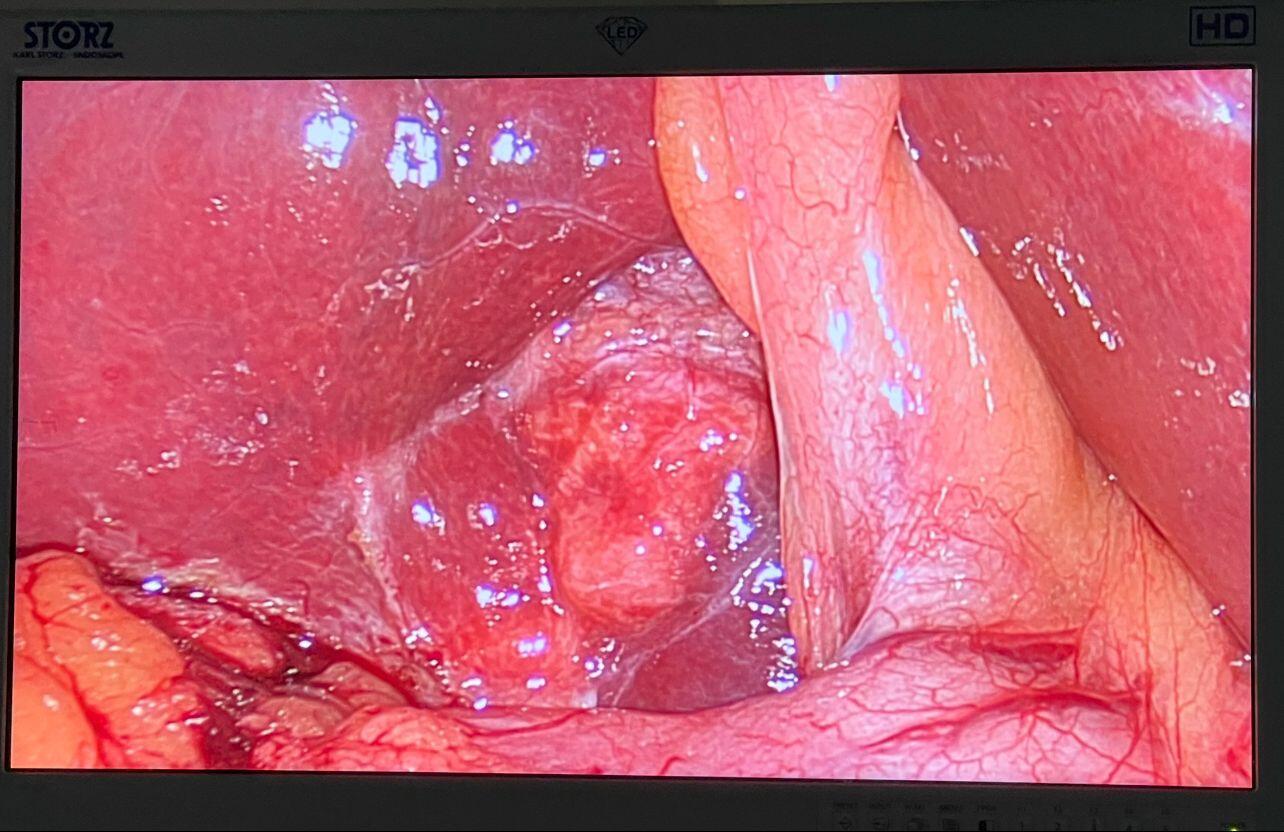

After 4 weeks of Albendazole, we performed Laparoscopic Hydatid cyst excision with lavage, drain placement, and Cholecystectomy.

1x10 mm and 3x5 mm ports were used for the surgery.